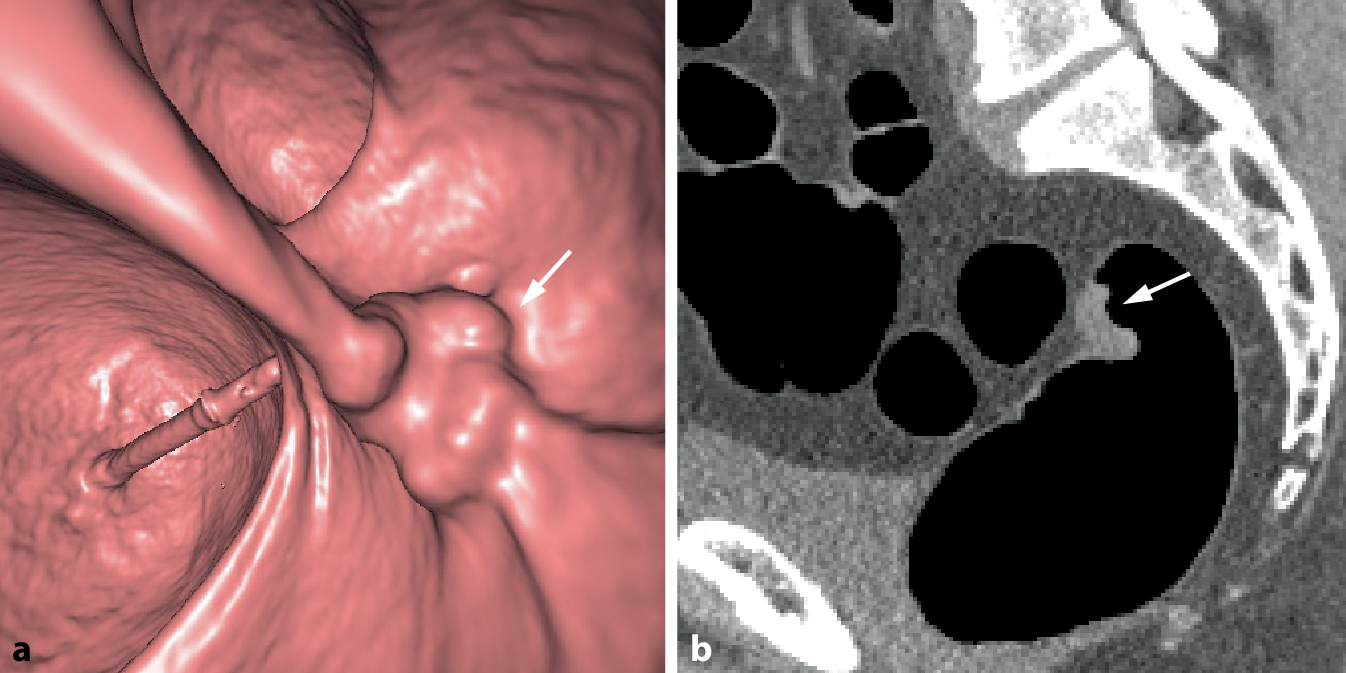

Asymptomatische Tumoren sind wesentlich kleiner und von geringerem Volumen als symptomatische KRK und daher radiologisch deutlich weniger auffällig und schwerer erkennbar. Der morphologische Aspekt ist eher polypös oder sattelförmig und seltener zirkulär oder stenosierend. Mittels Screening erkannte KRK weisen auch ein früheres radiologisches Tumorstadium auf. Suspekte Lymphknoten oder vaskuläre Invasionen sind seltener als bei symptomatischen Karzinomen (Abb. 7).

Abb. 7

Flaches Karzinom im oberen Rektum (G2, pT2, L0, V0, R0, pN0). a Die endoluminale 3D-Ansicht zeigt eine flache Wanderhabenheit mit nodulärer Oberfläche (Pfeil). b Das axiale und sagittale 2D-Bild (c) zeigen eine plaqueförmige Wandverbreiterung mit weichteildichter Struktur (Pfeil)

Bild vergrößern

Symptomatische Tumoren sind hingegen größer und bereits invasiver. Sie weisen häufiger eine zirkuläre Morphologie auf und engen das Darmlumen in größerem Ausmaß ein (Abb. 2; [32]).